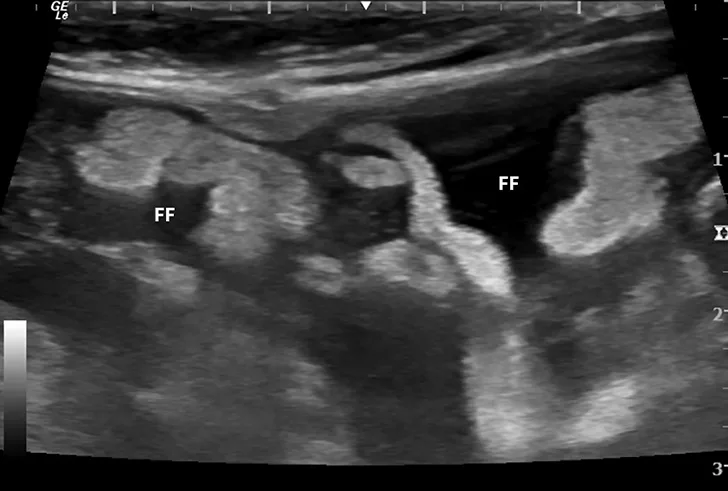

Dry FIP can manifest with organ dysfunction, uveitis, neurologic signs, fever, anemia, and/or lethargy and is caused by granulomas or immune complex deposition. Cats with wet FIP may have ascites or pleural effusion in addition to the aforementioned signs (Figure 1). Clinical presentation can vary from minor to life-threatening and involve almost any organ system.

FIGURE 1

Ultrasound image showing abdominal effusion in a cat with wet FIP. Anechoic fluid is present between organs, distending the abdomen. FF = free fluid; L = liver; S = spleen; K = kidney